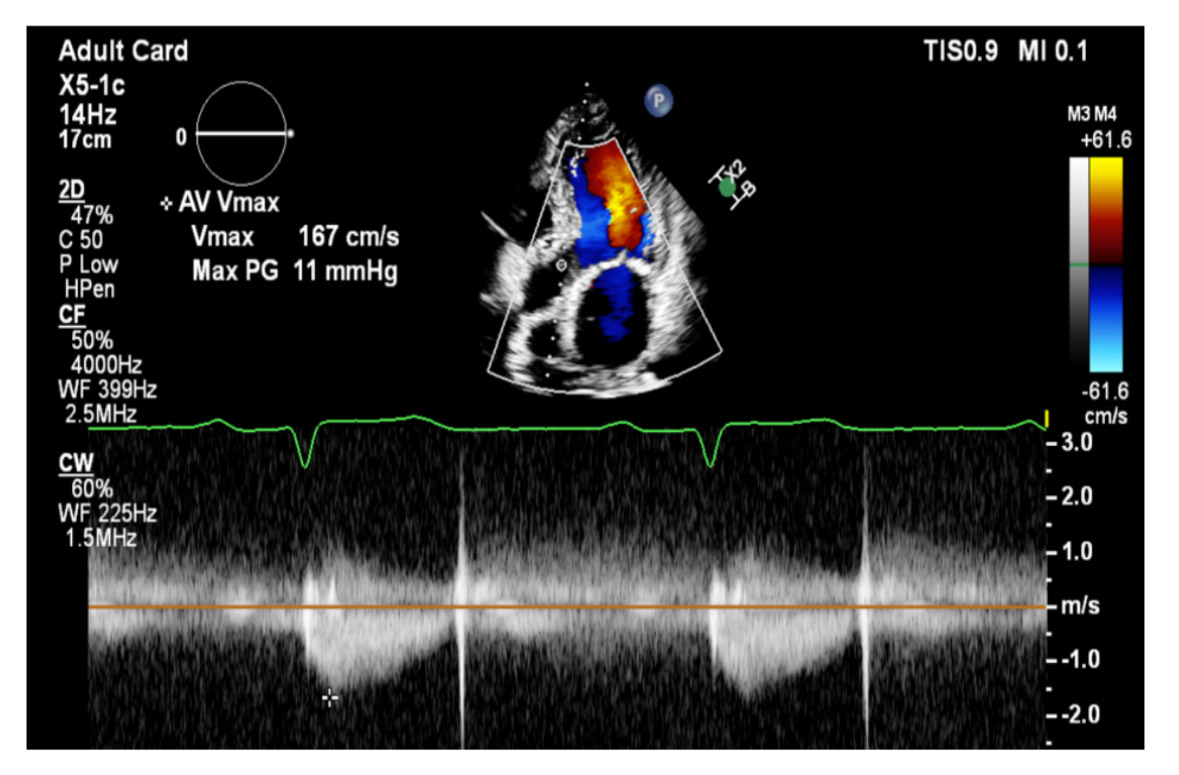

Post-TAVI aortography confirmed proper valve positioning with only a trivial paravalvular leak (PVL). The access sites were successfully closed using ProGlide and Angio-Seal devices. A total of 50 cc of Gadobutrol was used. Pre-discharge transthoracic echocardiography (TTE) confirmed good transcatheter heart valve (THV) positioning, no PVL, and a peak gradient of 6 mmHg. Renal function tests performed one week post-procedure showed no deterioration, with a creatinine level of 156 µmol/L.

Post-TAVI aortography confirmed proper valve positioning with only a trivial paravalvular leak (PVL). The access sites were successfully closed using ProGlide and Angio-Seal devices. A total of 50 cc of Gadobutrol was used. Pre-discharge transthoracic echocardiography (TTE) confirmed good transcatheter heart valve (THV) positioning, no PVL, and a peak gradient of 6 mmHg. Renal function tests performed one week post-procedure showed no deterioration, with a creatinine level of 156 µmol/L.